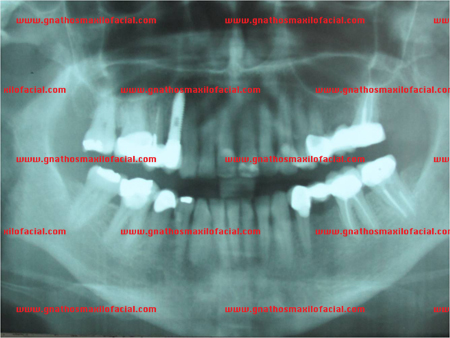

Un procedimiento de implante inmediato es aquel en el que se realiza una extracción dental y a continuación se inserta el implante en la misma sesión quirúrgica. Comúnmente se acompaña de colocación de aloinjerto óseo, para rellenar la separación entre las paredes del lecho de la extracción y la superficie del implante. El siguiente es un ejemplo clínico:

| Rx panorámica donde se observa resto radicular de premolar superior derecho junto a una lesión periapical del premolar adyacente | |